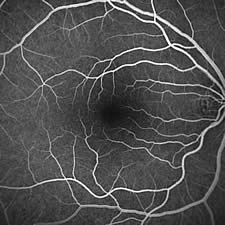

Diagnostik - Angiographie

Die Fluoreszenz-Angiographie (Gefäßdarstellung der Netzhaut mit einem fluoreszeierenden Farbstoff) ist das wichtigste diagnostische Verfahren in der Augenheilkunde. Es wird heute bei fast allen Patienten, die an einer Erkrankung der Netzhaut oder der Makula (Stelle des schärfsten Sehens der Netzhaut) leiden, durchgeführt. Zur Angiographie wird dem Patienten eine kleine Menge eines fluoreszeierenden und vollkommen ungiftigen Farbstoffs in eine Armvene injiziert. Nach etwa 20 Sekunden erscheint der Farbstoff am Augenhintergrund und wird dort mit einer sehr lichtempfindlichen Laserkamera photographiert. Die Lichtbelastung des Auges ist hierdurch ausgesprochen gering und die Untersuchung für den Patienten nicht belastend. Mit der Angiographie lassen sich Veränderungen der Netzhautgefäße wie Entzündungen, Thrombosen oder Embolien, eine Wassereinlagerung in der Netzhautmitte (Makulaödem), Membranbildungen auf der Netzhaut oder Veränderungen der Pigmentschicht des Augenhintergrundes feststellen. Am wichtigsten ist die Angiographie bei der Unterscheidung der trockenen von der feuchten Form der alterskorrelierten Makuladegeneration, weil bei der feuchten Makuladegeneration heute eine rasche und effektive Therapie in Form einer intraokularen Injektion eines Gefäßhemmstoffs möglich ist. Für besonders schwierig zu diagnostizierende Erkrankungen steht uns mit der Infrarot-Angiographie ein zweites diagnostisches Verfahren zur Verfügung, mit dem der Beginn einer feuchten Makuladegeneration oft früher erfasst werden kann als mit der Standard-Angiographie. |